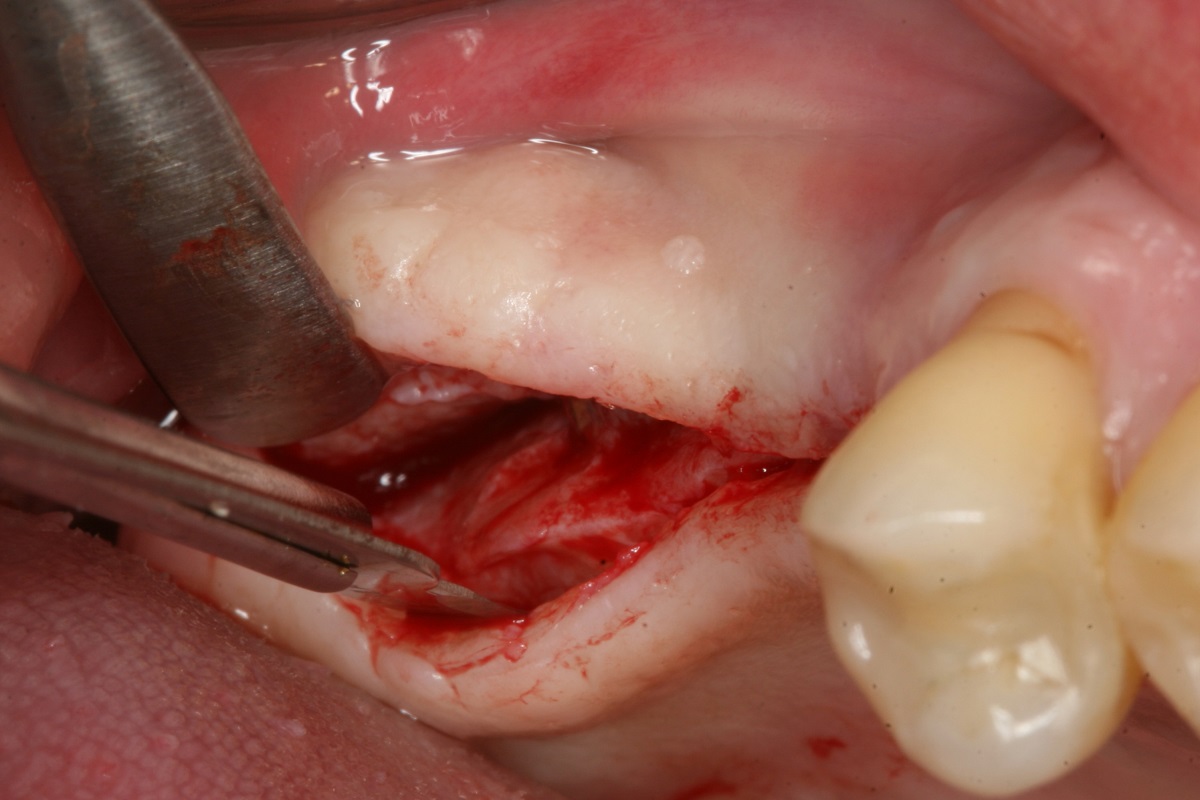

12/14 - Uncovering of implants 10 weeks post-op

Two-stage sinus lift with maxresorb® & collprotect® - Dr. S. Kistler

13/14 - Insertion of healing abutments